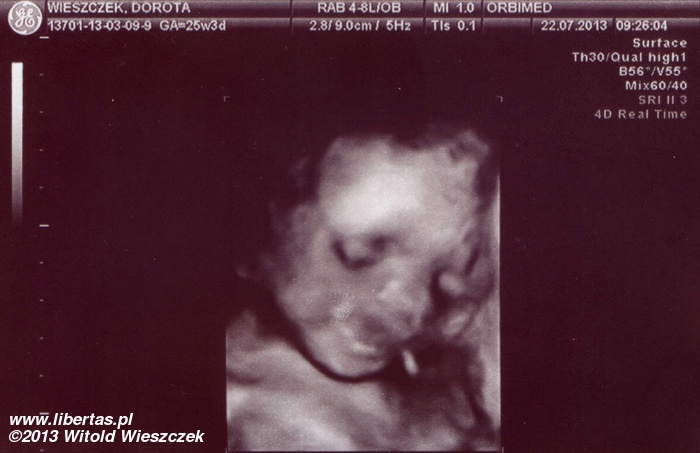

Księżniczka Dobrawa Wieszczek urodziła się 20 września 2013 roku o godzinie 8:50 w Szpitalu Wojewódzkim w Tychach. Chyba nie mogła się doczekać, bo swoje przyjście na świat przyspieszyła o ponad miesiąc, ważyła więc tylko 2140 gram i rozciągała się na długość 46 cm. Ale w skali Apgar dostała pełne 10 punktów i choć z tymi wszystkim rurkami wyglądała kosmicznie, to była zdrowa i czuła się świetnie.